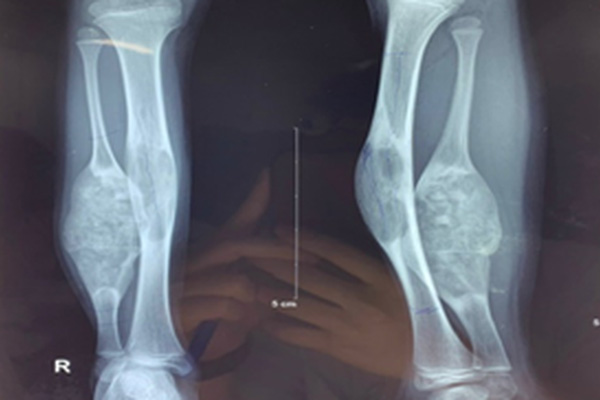

Hình ảnh phim chụp chân bé gái trước mổ.

Qua khám và làm các xét nghiệm, bé được chẩn đoán loạn sản xơ xương cẳng chân phải. Các bác sĩ Khoa Chấn thương - Chỉnh hình đã hội chẩn và quyết định phẫu thuật để lấy lại chức năng vận động cho cháu bé.

Trong quá trình phẫu thuật, các bác sĩ đã tiến hành cắt khối u xương mác để lại màng xương, đục bỏ khối u xương chày - ghép đoạn xương mác đối bên khoảng 12 cm, cố định bằng các phương tiện kết hợp xương.